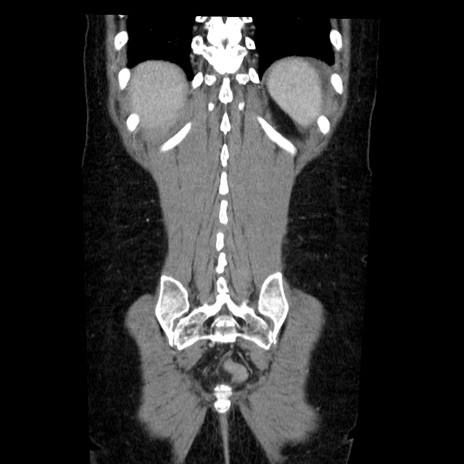

症例6(冠状断像)

【症例】50歳代女性

【主訴】下腹部痛

【現病歴】本日朝より下痢2回あり。 昼食を食べた後、嘔吐3回、下腹部痛認め、症状軽快せず、当院救急搬送。

最終食事:本日昼(生ものなし)。 昨日の夜、刺身を食ぺたとのこと。周囲に同様の症状の者なし。普段、排便は毎日あるとのこと。

【既往歴】卵巣癌術後(8年前に当院で卵巣摘出)

【身体所見】 意識清明、腹部:平坦、腸蠕動音→、やや硬、下腹部自発痛・圧痛あり、反跳痛あり、筋性防御なし。

【データ】WBC 16000、CRP 0.01